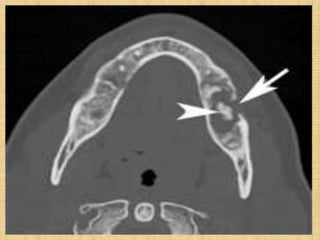

• #12 (a) CT scan (bone windowing) demonstrates a nonexpansile, osteolytic lesion (arrow) within the right mandible. Perimandibular soft-tissue inflammatory change (arrowheads) is also present.

• #15 CT scan reveals an osteolytic lesion (arrow) containing a bony sequestrum (arrowhead) within the left mandibular body.